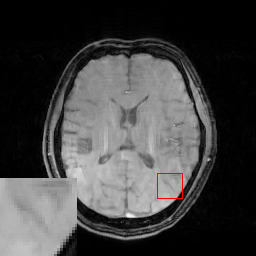

In the CS-MRI inversions, the zero-filled MR images usually serve as the starting point in the iterative optimization. Although the iterative de-aliasing can effectively remove the artifacts and achieve much more pleasing visual quality compared with zero-filled reconstruction, the distortion and information loss is inevitable in the reconstruction. To further illustrate this phenomenon, we compare the pixel-wise reconstruction errors among the zero-filling reconstruction and other reconstruction models of the MR image in Figure 2.

We take the difference between the absolute reconstruction error of zero-filled and the compared CS-MRI methods and only keep the nonnegative values, which can be formulated as

md=(|xfsx¯p||xfs𝒵(y)|)+.subscript𝑚𝑑subscriptsubscript𝑥𝑓𝑠subscript¯𝑥𝑝subscript𝑥𝑓𝑠𝒵𝑦m_{d}={\left({\left|{{x_{fs}}-{\overline{x}_{p}}}\right|-\left|{{x_{fs}}-{\cal Z}(y)}\right|}\right)_{+}}. (8)

Where the operator ()+subscript{\left(\cdot\right)_{+}} set the negative values to zero. We only keep the nonnegative values in the map, which results the filtered difference map. We show the corresponding filtered difference map mdsubscript𝑚𝑑m_{d} in figure 3 in the range [0 0.2]. The bright region means the better accuracy of zero-filled reconstruction. We observe the zero-filling reconstruction provide better reconstruction accuracy on some regions, indicating the information loss in the reconstruction occurs.

Figure 3: The filtered difference map d𝑑d between the reconstruction errors of the zero-filled reconstruction and recent CS-MRI inversions.